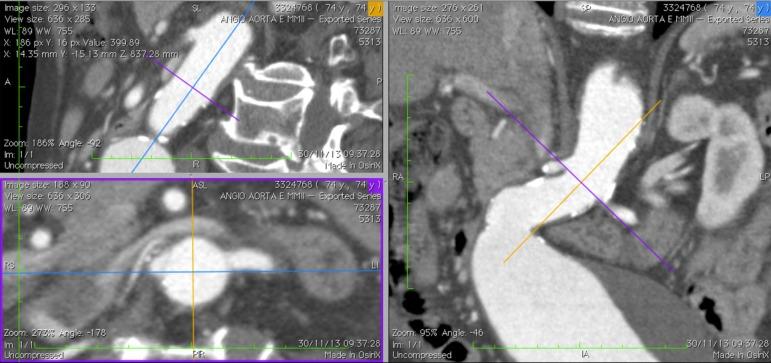

Endovascular aneurysm repair requires the precise deployment of the graft. In order to achieve accurate positioning, the anatomical and morphological characteristics of the aorta and its branches is mandatory. Software that perform three dimensional reformatting of multislice tomographic images, allow for the study of the whole aorto-iliac axis and the perpendicular visualization of the origin of the renal arteries. The correct length of the proximal neck can be evaluated and adequate graft fixation and sealing may be foreseen. A technique is presented, using an software, for the orthogonal correction of the position of the renal arteries in relation to the proximal neck, which may guide the radioscopic orientation intraoperatively.

Within a multiplanar tomographic image reconstruction, virtual triangulation allows for the three dimensional orthogonal correction of the renal arteries' ostia position. The predetermined best angulations for visualization are annotated and used for the positioning of the surgical C-arm.

RESULTS/DISCUSSION: Some authors discuss that the anatomic position of the renal vessels seen on the tomographic scan can change during the surgical procedure. It is known that the renal arterys' angular positioning does not alter, even after insertion of stiff guidewires, introducers, and the endograft itself. Therefore, it is possible, using concepts of spacial geometry and orthogonal correction, to predict the ideal bidimensional intraoperative positioning of the radioscopy device in order to reproduce the optimized renal artery ostial projection, ensuring the best accuracy during endograft deployment.